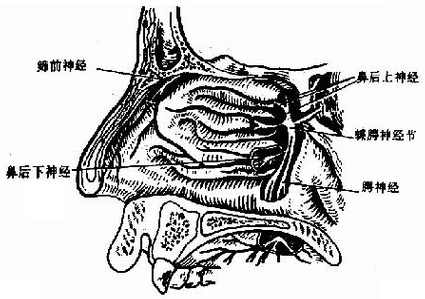

2.感觉神经主要来自三叉神经的第一支(眼神经)和第二支(上颌神经)的分支。

眼神经经鼻睫神经分出筛前神经,分布于鼻中隔和鼻腔外侧壁的前部。

上颌神经在翼腭窝形成蝶腭神经节,分出鼻后上神经和鼻后下神经,前者分布于鼻中甲以上部分的鼻腔及鼻窦,后者分布于中鼻道以下的鼻腔(图1-12)。

图1-12 鼻腔神经分布

上颌神经还分出上牙槽神经后支及眶下神经,前者分布于上颌窦及牙槽;后者分布于鼻前庭、鼻底及下鼻道前段。